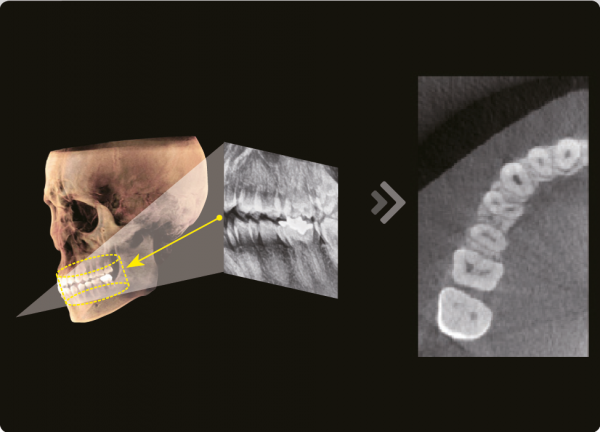

3D и 2D в одной программе

Используя 2D и 3D изображения одновременно мы получаем множество преимуществ. Нет необходимости в двух различных программах , что демонстрирует пациенту более профессиональный подход к диагностике и планированию лечения.